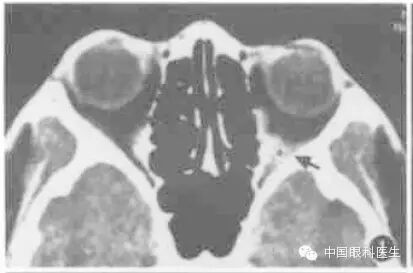

眶内静脉曲张常规CT扫描时多不显影,或仅显示小部分病变,欲观察病变全部范围可行颈部加压检查(图1,图2)。将血压计袋缠于患者颈部,摆好位置,加压至5.33kPa(高于静脉压),再行扫描检查,扫描完毕后立即将气囊放松。

图1左眶静脉曲张,平扫CT显示左眶后少许软组织密度(箭头)

图2同例静脉曲张加压后CT显示左眼球明显出土,球后出现巨大高密度软组织块影(箭头)